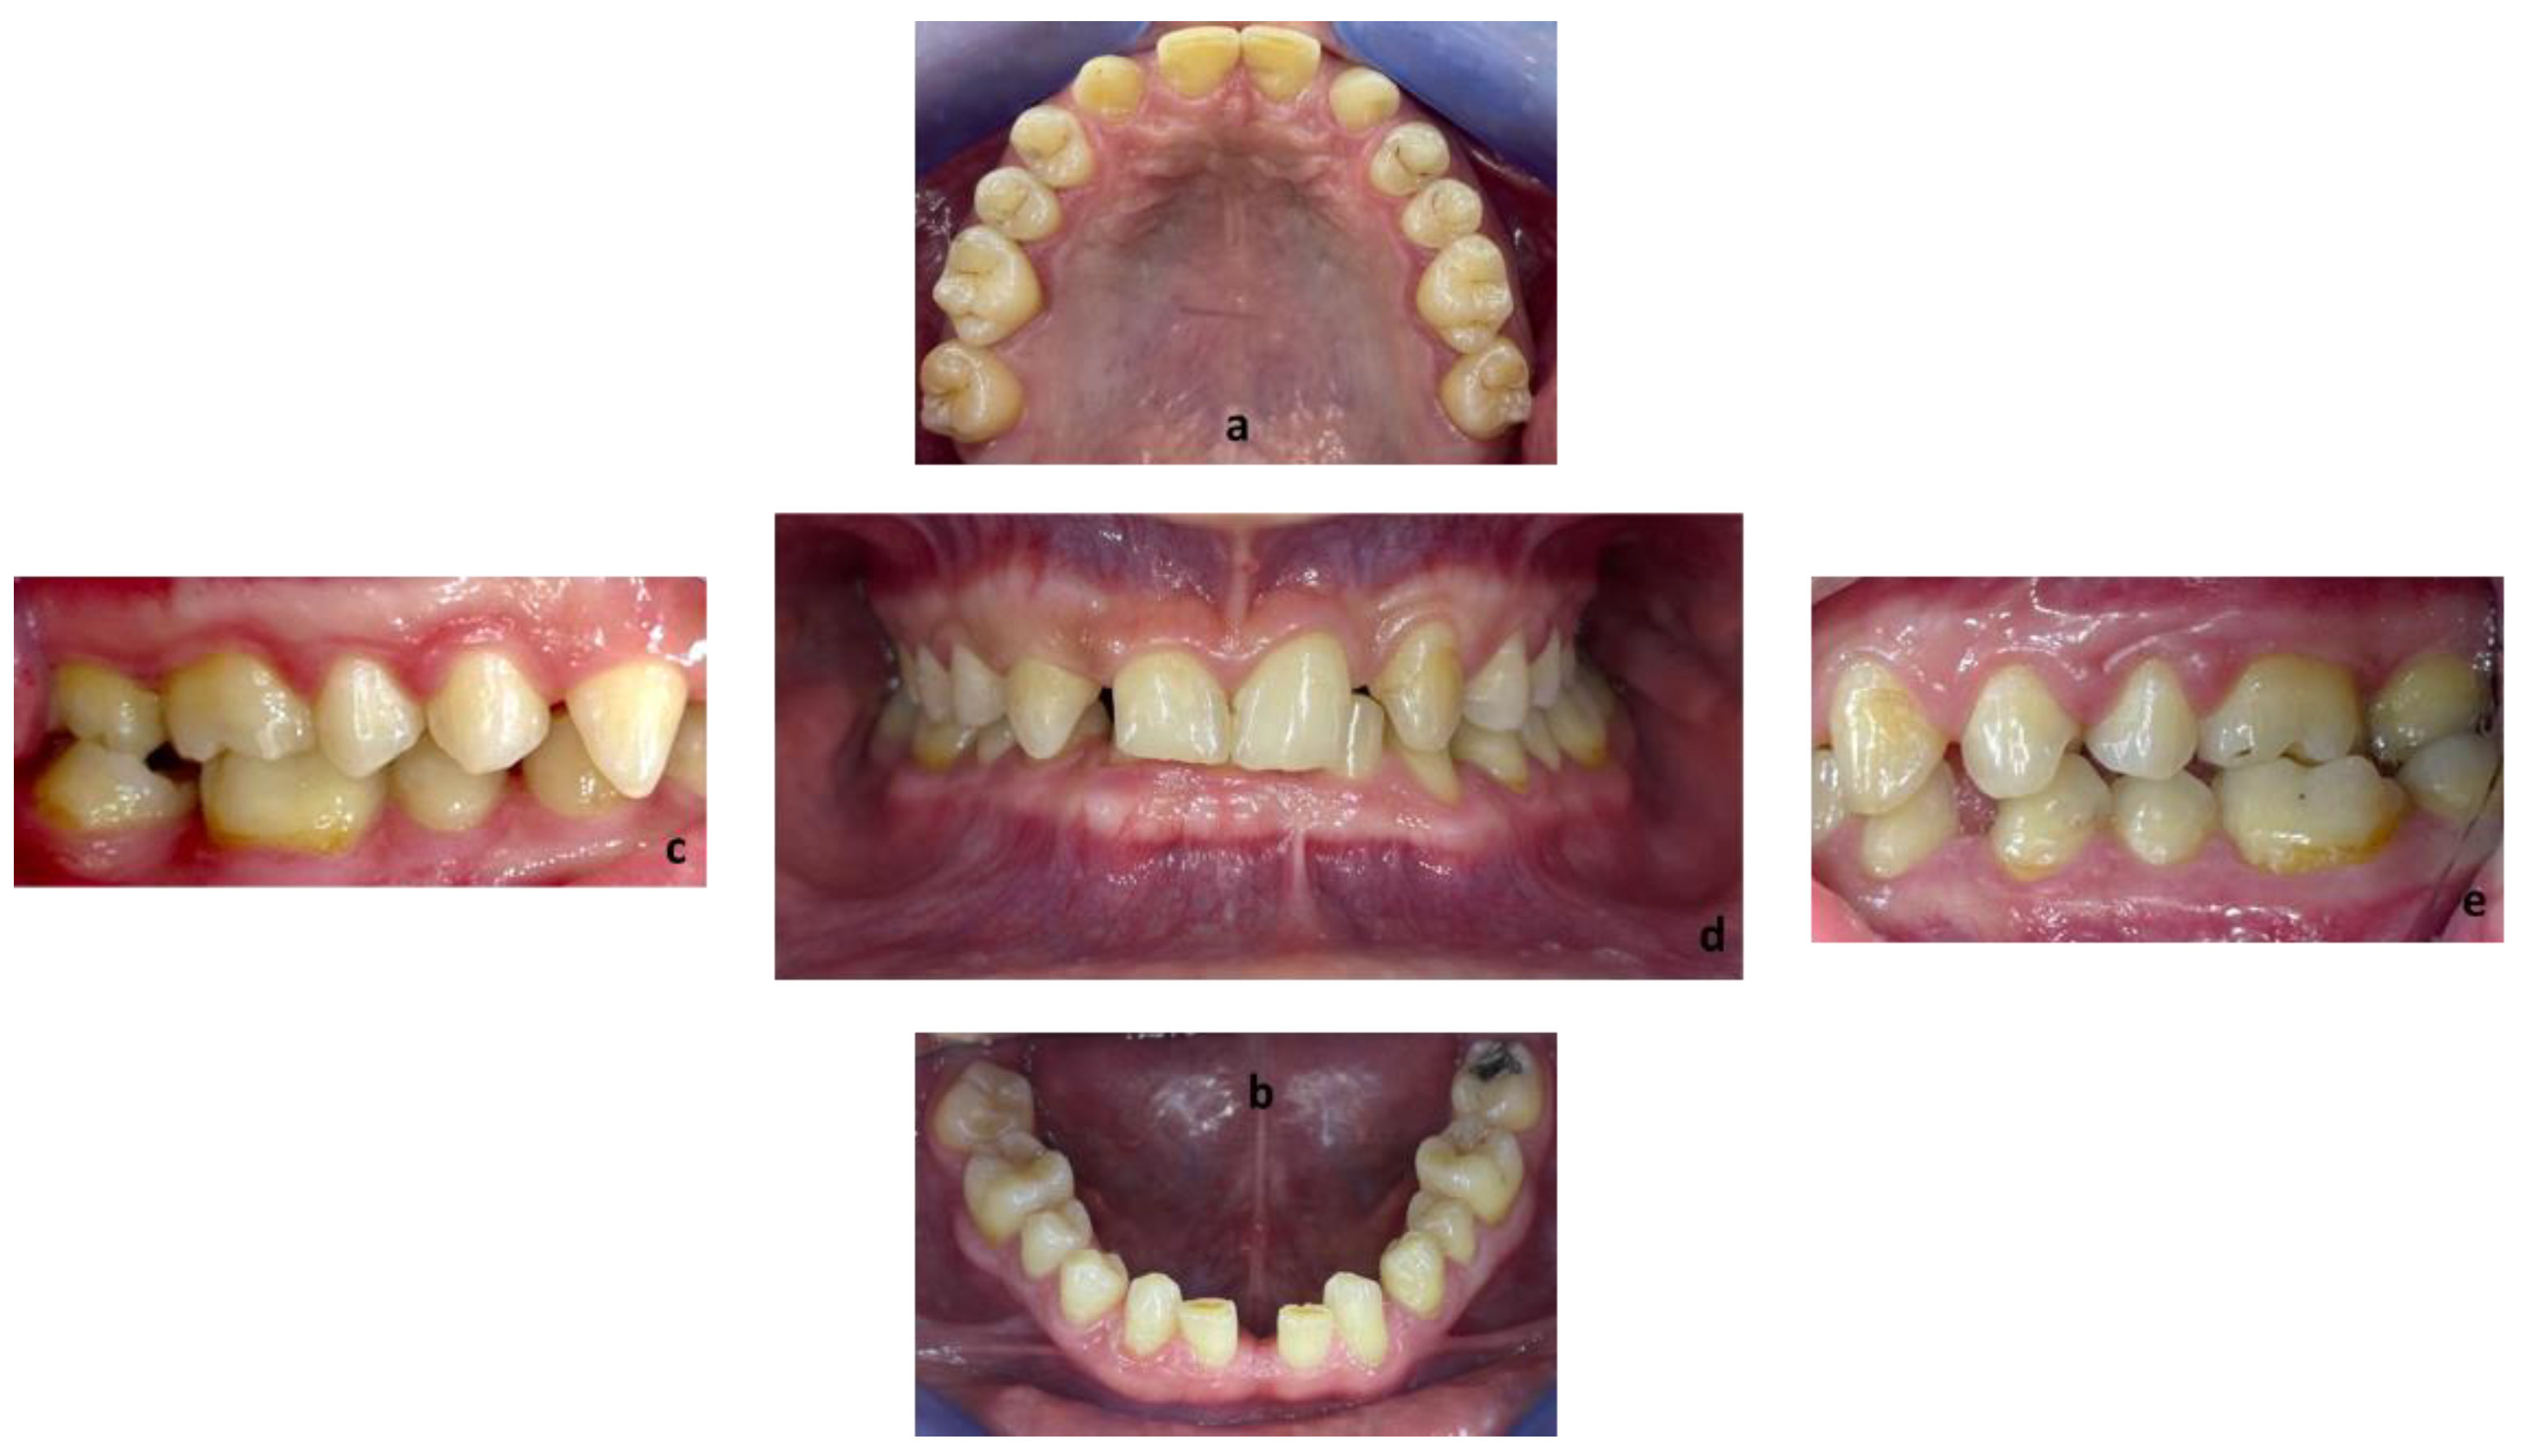

Figure 2.

Endobuccal views: (a) maxillary arch, (b) mandibular arch, (c) right side occlusion, (d) front bite, (e) left side occlusion.

Exobuccal clinical assessment showed a leftward convergence of the facial lines, an asymmetric smile, and the presence of oral corridors. The profile examination showed a lowering of the lower face, an open naso-labial angle, a concave subnasal profile with a reduced cervical-chin distance and a biretrochelia.

Endobuccal clinical assessment revealed dental agenesis of the upper left and right lateral incisors and lower left and right central incisors, generalized small teeth size, infiltrated maxillary grooves, and an amalgam restoration on the occlusal surface of the lower left second molar. Occlusal analysis showed complete overbite, a left unilateral articular inversion on the two upper left molars, an Angle Class I canine and molar on the right side and an Angle Class II canine and molar on the left side. In addition, the anterior overhang is reduced, so the patient is in class II division 2.

The radiological examination revealed voluminous dental pulps, apical root resorptions on the lower molars and the absence of the upper left third molar and the two lower third molars.